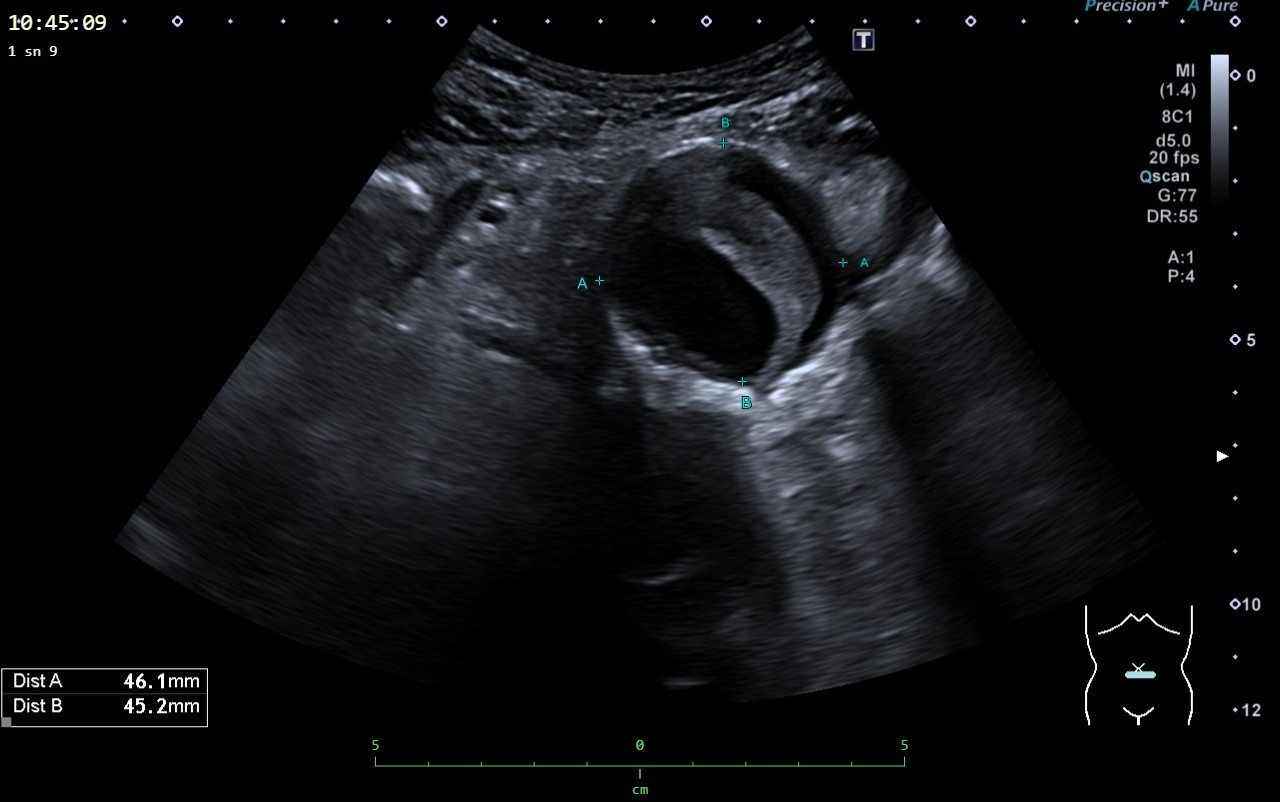

Fig. 5. 61-year-old patient with an infrarenal abdominal aortic aneurysm with a thrombotic rim intraluminal.